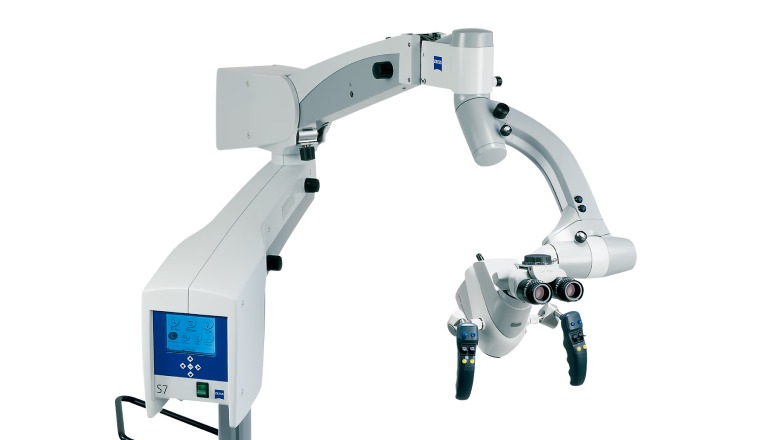

マイクロスコープ

一般的な歯科治療の場合、狭くて暗い口腔内を肉眼または拡大鏡を使って処置するため、どうしても見えない部分が多く、医師の経験や勘に頼って行われることが少なくありません。

そのため、虫歯の感染部位の取り残しや削りすぎ、詰め物や被せ物の不適合によって、治療した歯が再び悪化し、再治療になるケースが多く見られます。

しかし歯は何度も治療に耐えられないため、再治療を繰り返すことで早期に抜歯となるリスクも高まります。

こうした問題を解決するのがマイクロスコープ(歯科用顕微鏡)を用いた治療です。

マイクロスコープのメリット

- 肉眼や拡大鏡で見えない細部まで確認できる

- 見逃しや治療ミスの防止

- 治療回数や再治療の減少

- 写真・動画による治療説明が可能

マイクロスコープは最大34倍まで拡大でき、明るい視野を確保することで、従来見えなかった部分も鮮明に確認することが可能になります。

これにより必要以上に削ることなく、感染部位だけを的確に除去し、より適合精度の高い補綴物(詰め物・被せ物)を作成でき、歯に対して最小侵襲(体への最小の負担)で処置を行えるようになりました。

つまり、1回で治療を終了させて再治療になるリスクを大幅に減らすことができるのです。

拡大鏡(ルーペ)とマイクロスコープの違い

| マイクロスコープ | 拡大鏡(ルーペ) | |

|---|---|---|

| 拡大率 | 2~34倍 | 2〜8倍 |

| 視野の広さ | 狭い(ピンポイントで見る) | 広い(肉眼に近い) |

| 見える細かさ | 微細構造まで確認可能 | 限界あり |

| 特徴 | 高精度・録画も可能 | 手軽・広範囲が見える |

当クリニックで導入している

マイクロスコープ

(※2024年時点の目安)

当クリニックでは、マイクロスコープを2008年から導入し、国内外でもトレーニングを受け、現在ほとんどすべての治療に用いて良好な結果を得ています。

また、2013年には日本顕微鏡歯科学会の認定医を取得し、世界標準治療のガイドラインに沿った治療を目指しています。